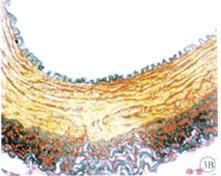

2.3 血管组织切片显微镜下观察 (1)对照组:内膜极度增厚,几乎堵塞管腔,可见附壁血栓。新生内膜主要由血管平滑肌细胞、炎性细胞、纤维母细胞和大量细胞间质构成(图2A,B;图见插页)。(2)实验组:内膜增生较对照组明显减轻,新生内膜主要成分为血管平滑肌细胞及胞外基质,远端流出道吻合口内膜增生又较近端流入道明显减轻。移植的静脉片段中膜明显增厚,且有发达的内弹力膜,呈动脉样结构改变,少量的平滑肌细胞呈泡沫样改变,未见脂纹和胆固醇结晶(图2C,D,图3A,B;图见插页)。

图3 实验组间置静脉内膜增生情况

Fig 3 Intimal hyperplasia of interpositional vein in experimental group

, http://www.100md.com

A:HE×10; B: V/G×10